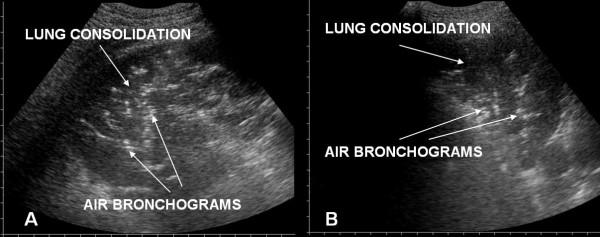

Ultrasound examination was focalised on finding in the two groups the presence of: 1) alveolar-interstitial syndrome (AIS) 2) pleural lines abnormalities 3) absence or reduction of "gliding" sign 4) "spared areas" 5) consolidations 6) pleural effusion 7) "lung pulse".AIS was found in 100% of patients with ALI/ARDS and in 100% of patients with APE (p = ns). Pleural line abnormalities were observed in 100% of patients with ALI/ARDS and in 25% of patients with APE (p < 0.0001). Absence or reduction of the 'gliding sign' was observed in 100% of patients with ALI/ARDS and in 0% of patients with APE. 'Spared areas' were observed in 100% of patients with ALI/ARDS and in 0% of patients with APE (p < 0.0001). Consolidations were present in 83.3% of patients with ALI/ARDS in 0% of patients with APE (p < 0.0001). A pleural effusion was present in 66.6% of patients with ALI/ARDS and in 95% of patients with APE (p < 0.004). 'Lung pulse' was observed in 50% of patients with ALI/ARDS and in 0% of patients with APE (p < 0.0001). All signs, except the presence of AIS, presented a statistically significant difference in presentation between the two syndromes resulting specific for the ultrasonographic characterization of ALI/ARDS.

超声检查重点在于在两组中发现以下情况:1)肺泡-间质综合征(AIS);2)胸膜线异常;3)“滑动”征缺失或减弱;4)“ spared区域”;5)实变;6)胸腔积液;7)“肺搏动”。AIS在100%的ALI/ARDS患者和100%的APE患者中均有发现(p=无显著性差异)。胸膜线异常在100%的ALI/ARDS患者和25%的APE患者中观察到(p<0.0001)。“滑动”征缺失或减弱在100%的ALI/ARDS患者和0%的APE患者中观察到。“ spared区域”在100%的ALI/ARDS患者和0%的APE患者中观察到(p<0.0001)。实变在83.3%的ALI/ARDS患者中存在,在0%的APE患者中存在(p<0.0001)。胸腔积液在66.6%的ALI/ARDS患者和95%的APE患者中存在(p<0.004)。“肺搏动”在50%的ALI/ARDS患者和0%的APE患者中观察到(p<0.0001)。除AIS的存在外,所有体征在两种综合征之间的表现上均存在统计学显著差异,从而对ALI/ARDS的超声特征具有特异性。

Pleuroparenchimal patterns in ALI/ARDS do find a characterization through ultrasonographic lung scan. In the critically ill the ultrasound demonstration of a dyshomogeneous AIS with spared areas, pleural line modifications and lung consolidations is strongly predictive, in an early phase, of non-cardiogenic pulmonary edema.

ALI/ARDS中的胸膜实质模式可通过超声肺部扫描进行特征描述。在危重症患者中,超声显示不均匀的AIS伴 spared区域、胸膜线改变和肺实变在早期强烈提示非心源性肺水肿。